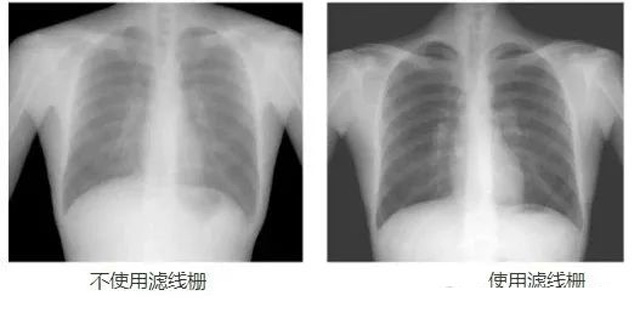

DR影像X射線在醫(yī)學(xué)檢查成像有著廣泛的使用。但是它的散射線影響成像質(zhì)量問題。濾線柵的發(fā)明使用很好的解決了這個(gè)問題,構(gòu)造簡單鉛條粗,密度和柵比規(guī)格單一,能減散射線但吸收較多原發(fā)射線。伴隨這醫(yī)療影像設(shè)備技術(shù)的發(fā)展,這個(gè)濾線柵的工藝制造技術(shù)有改進(jìn),鉛條變薄,柵密度和柵比有更多的選擇。特別是材料方面有新組合,填充物也依不同成像要求優(yōu)化。特別是移動(dòng)DR這類型的DR設(shè)備的出現(xiàn),濾線柵也設(shè)計(jì)成立方便拆卸形的,方便使用。被照體情況決定是否使用,更好平衡成像質(zhì)量與射線劑量。

放置方面:置于人體與片盒間,聚焦面朝向X線入射方向,X線焦點(diǎn)放鉛條會(huì)聚線上,不能反置,X線中心對準(zhǔn)濾線柵中心,左右偏移不超3cm,傾斜X線管要與鉛條排列方向平行。攝影時(shí)焦距改變不超焦距的25%;活動(dòng)式濾線器運(yùn)動(dòng)時(shí)間至少長于曝光時(shí)間的1/5;因吸收原發(fā)射線要適當(dāng)增加曝光條件;四肢薄位置一般不用濾線柵;不同千伏對應(yīng)不同柵比;立位胸片架、乳腺DR攝影等有各自特定濾線柵要求。